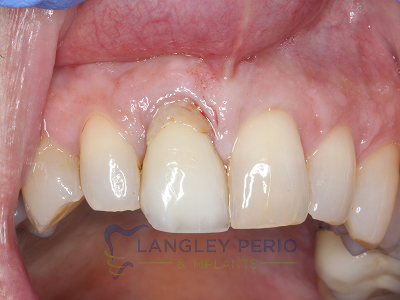

Case 2

Connective tissue grafting was done to cover exposed root surfaces to help to prevent root cavities from developing and reduce temperature sensitivity.